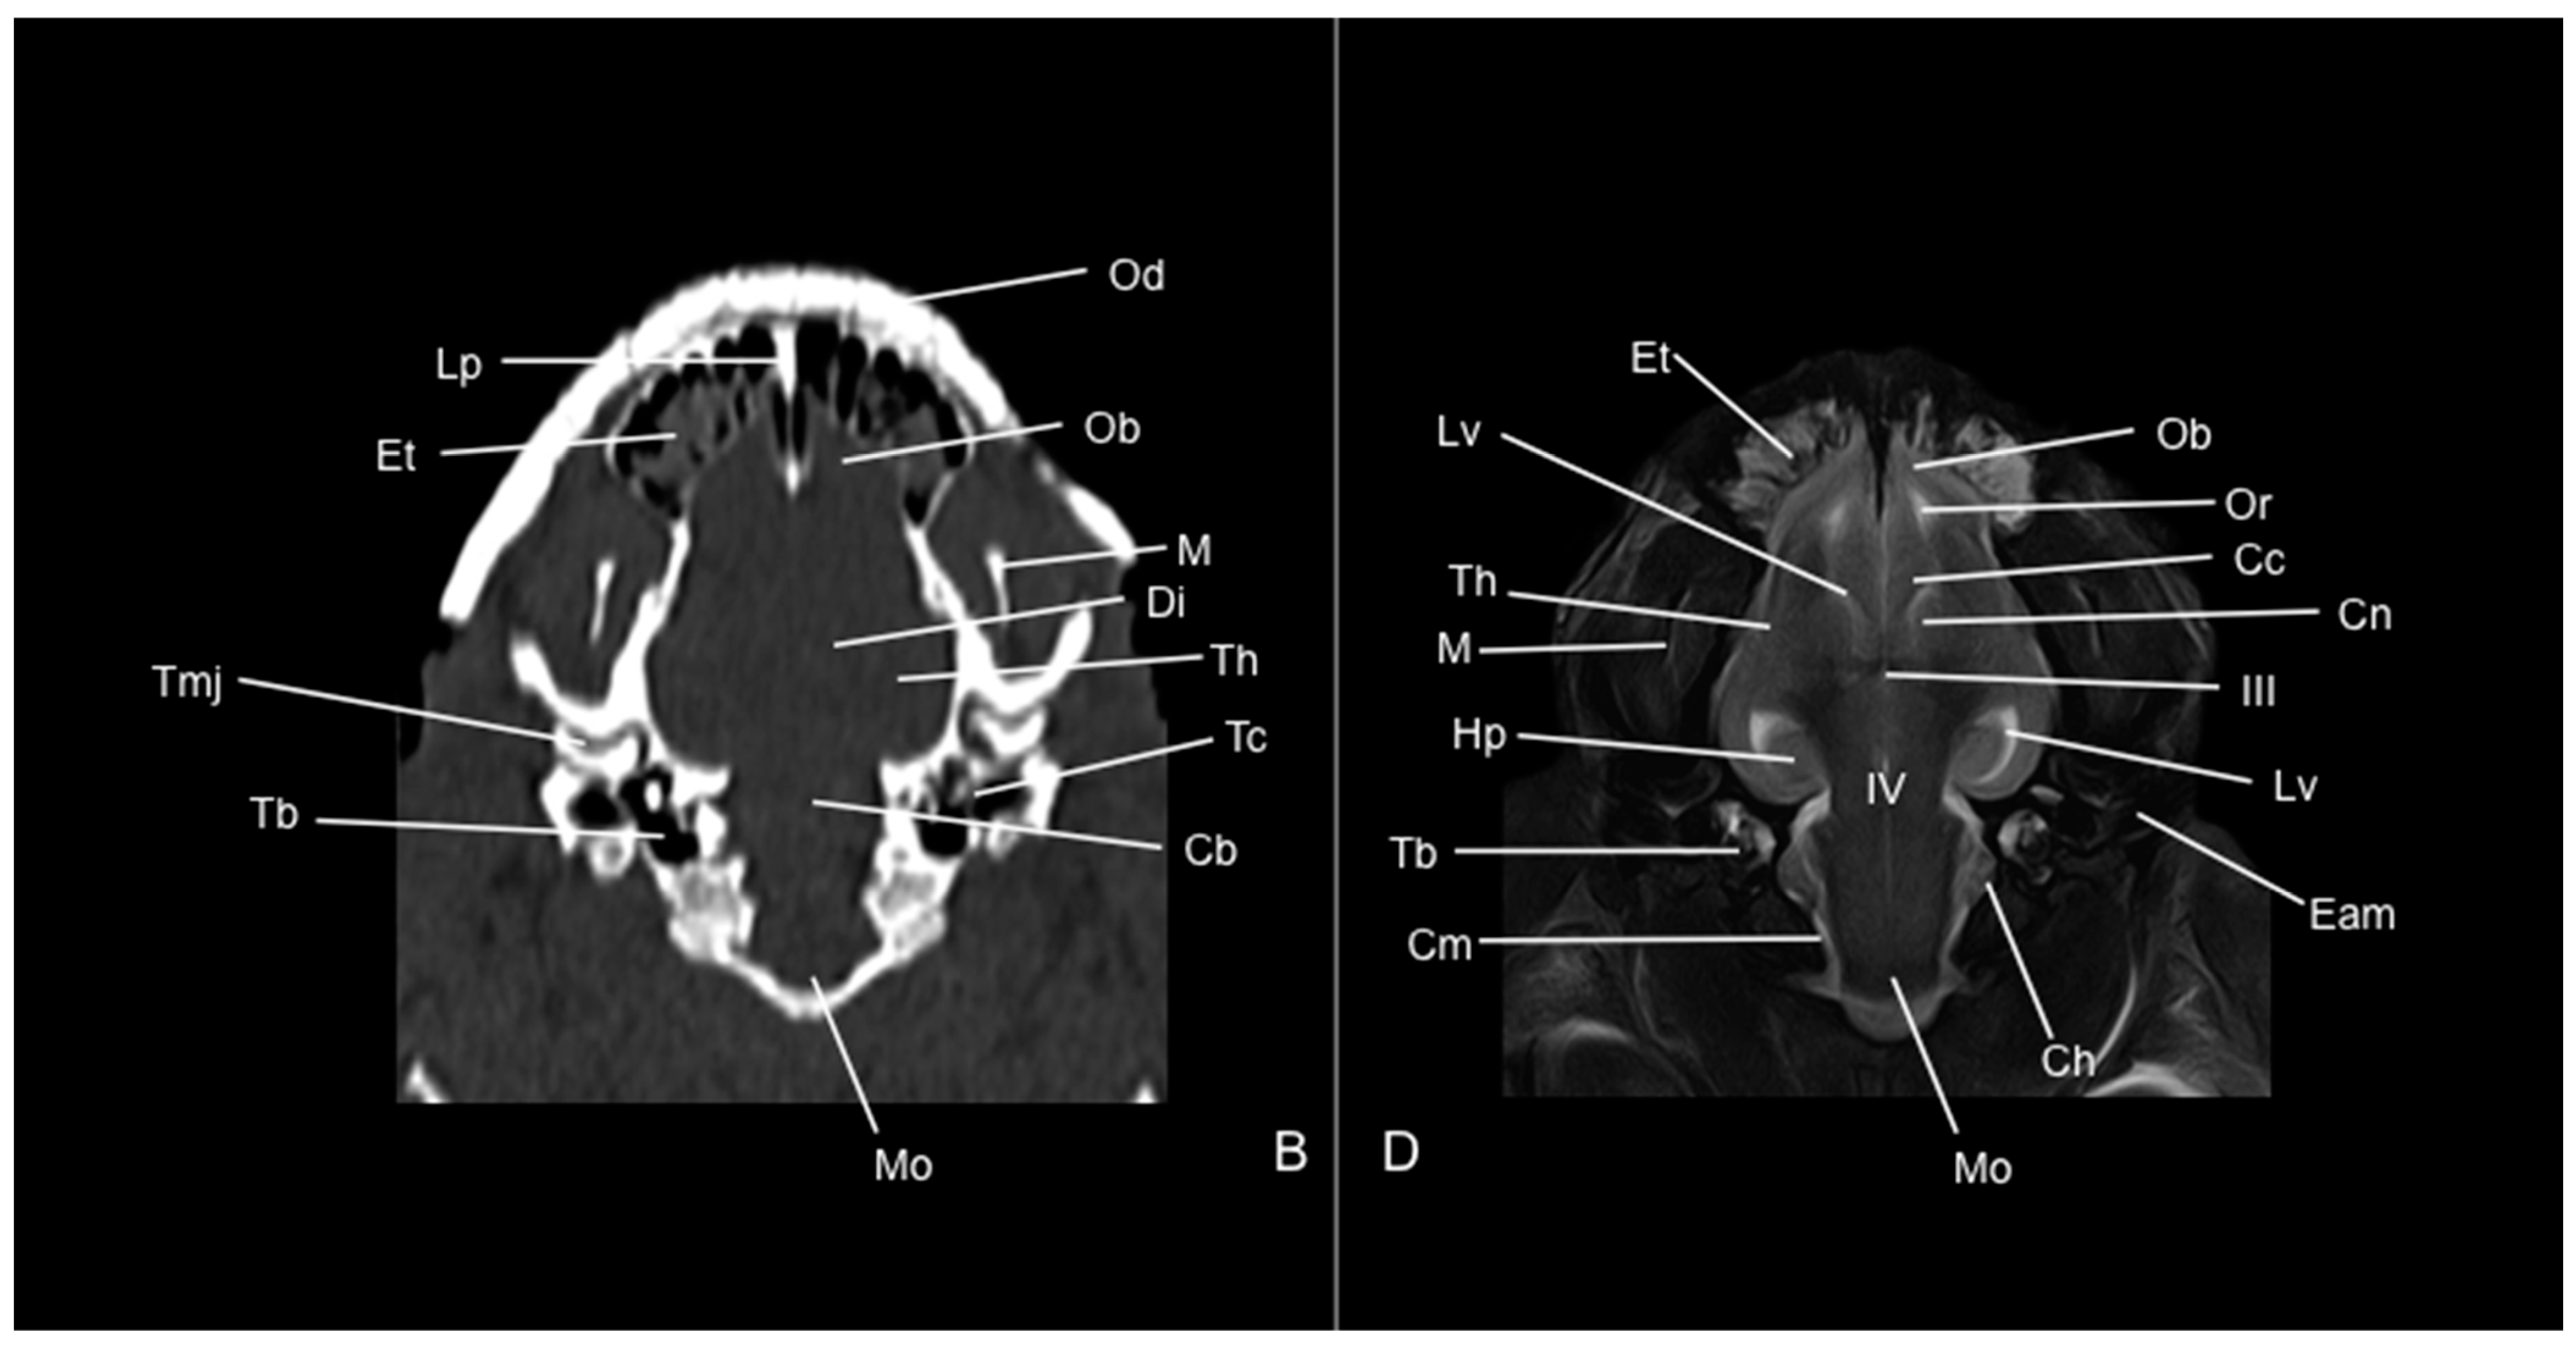

3. Results

3.1. Anatomical Study

3.2. Computed Tomography Study

3.3. Magnetic Resonance Imaging (MRI)